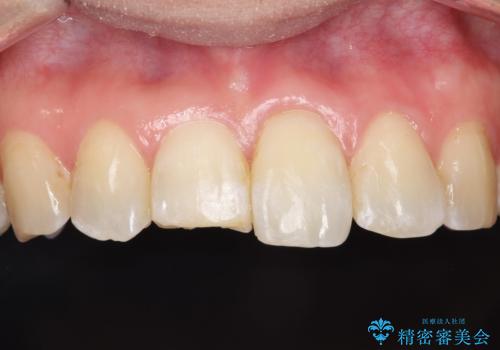

インビザラインによる矯正治療で前歯の歯並びを改善し、セラミッククラウン装着により歯の形態の回復をする計画としました。

矯正とセラミックを併用することで、より完成度の高い状態に仕上げることができました。